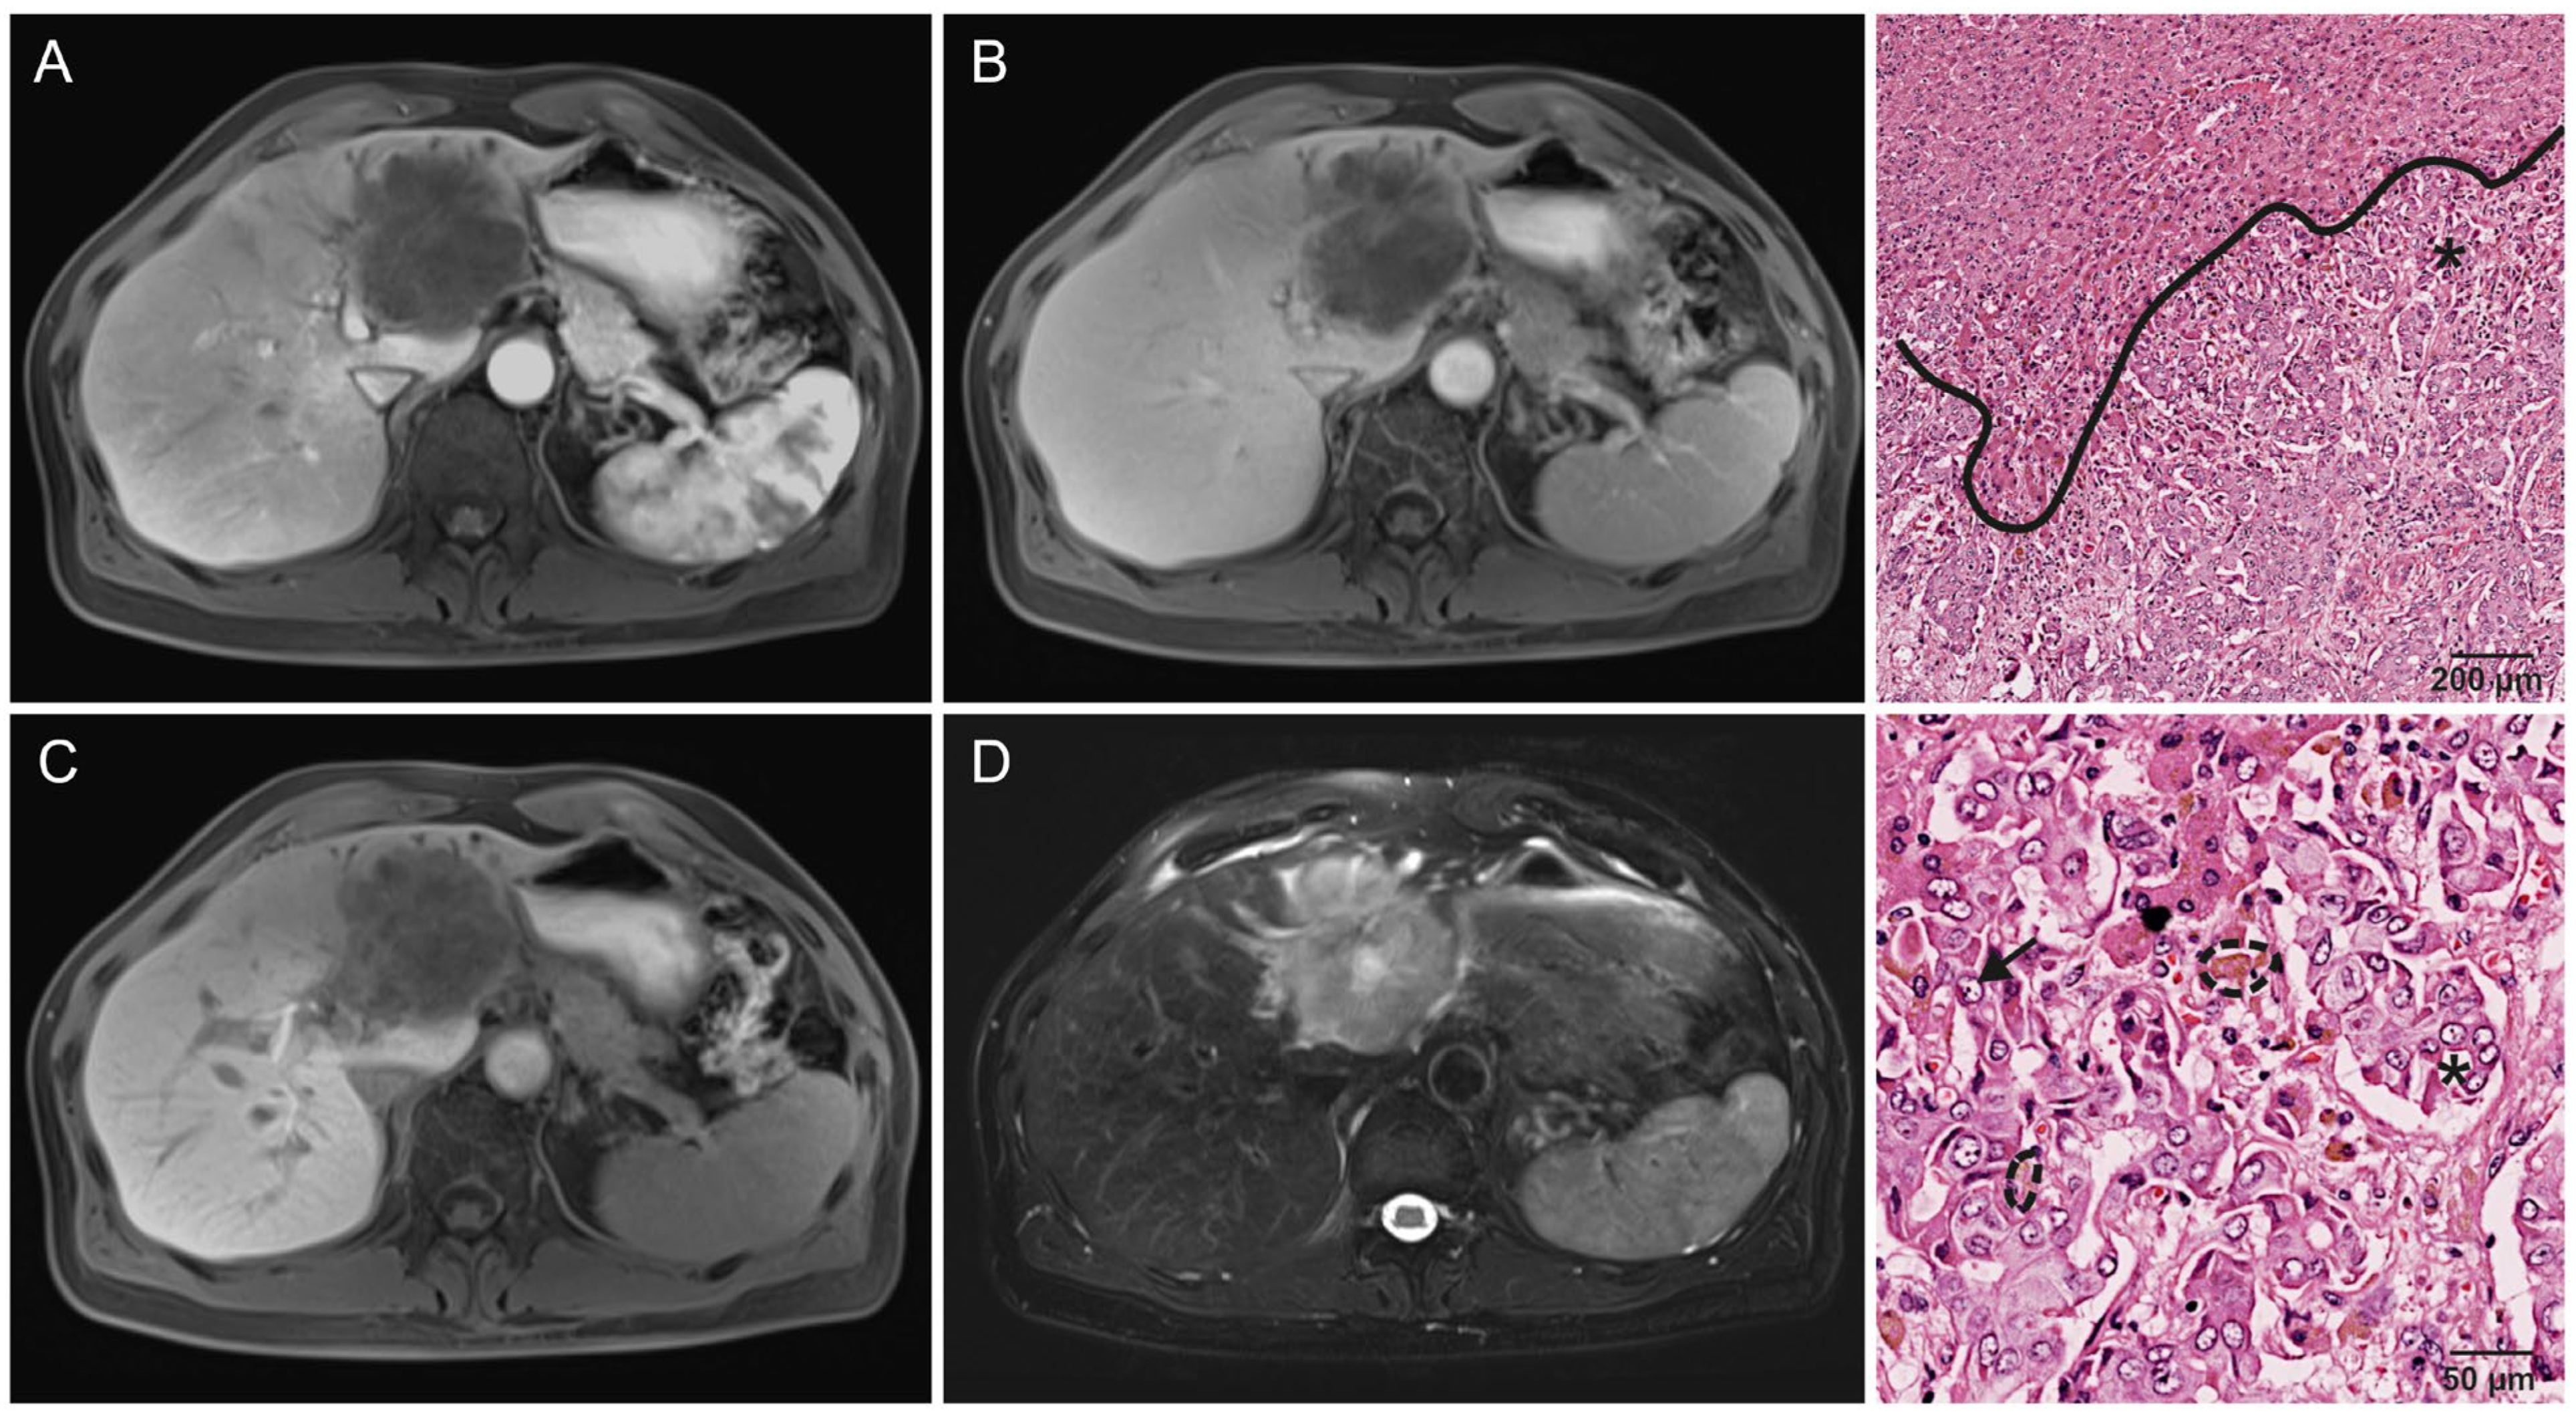

- Kang, Y.; Lee, J.M.; Kim, S.H.; Han, J.K.; Choi, B.I. Intrahepatic mass-forming cholangiocarcinoma: Enhancement patterns on gadoxetic acid-enhanced MR images. Radiology 2012, 264, 751–760. [Google Scholar] [CrossRef] [PubMed]

- Chung, Y.E.; Kim, M.J.; Park, Y.N.; Choi, J.Y.; Pyo, J.Y.; Kim, Y.C.; Cho, H.J.; Kim, K.A.; Choi, S.Y. Varying appearances of cholangiocarcinoma: Radiologic-pathologic correlation. Radiographics 2009, 29, 683–700. [Google Scholar] [CrossRef] [PubMed]

- Min, J.H.; Kim, Y.K.; Choi, S.Y.; Kang, T.W.; Lee, S.J.; Kim, J.M.; Ahn, S.; Cho, H. Intrahepatic Mass-forming Cholangiocarcinoma: Arterial Enhancement Patterns at MRI and Prognosis. Radiology 2019, 290, 691–699. [Google Scholar] [CrossRef] [PubMed]

- Jin, K.P.; Sheng, R.F.; Yang, C.; Zeng, M.S. Combined arterial and delayed enhancement patterns of MRI assist in prognostic prediction for intrahepatic mass-forming cholangiocarcinoma (IMCC). Abdom. Radiol. 2022, 47, 640–650. [Google Scholar] [CrossRef]

| Growth pattern | 0.005 * | ||

| Infiltrative | 70% (33/47) | 32% (6/19) | |

| Solid | 30% (14/47) | 68% (13/19) | |